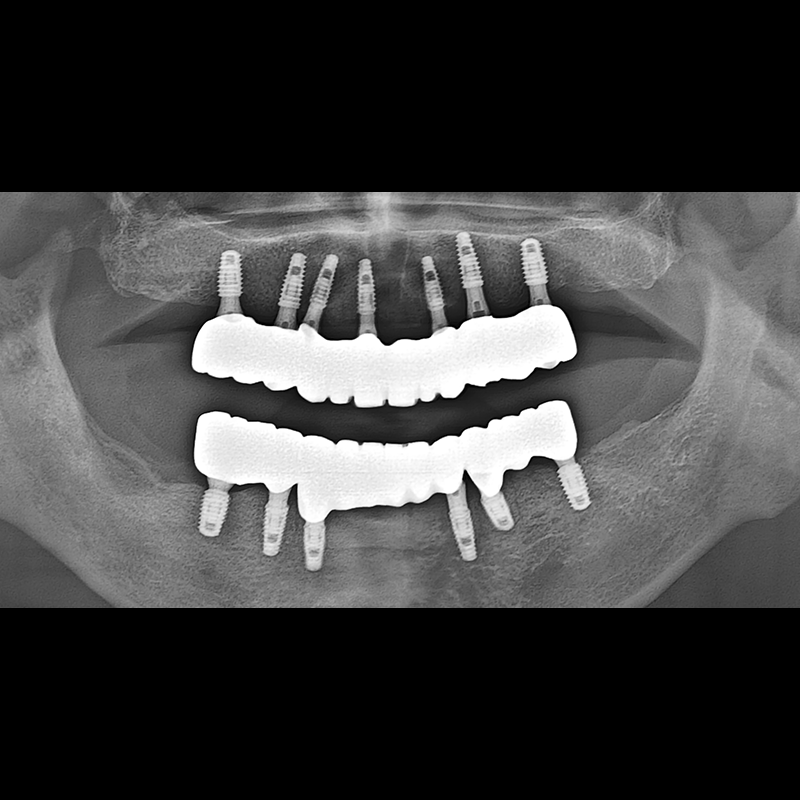

BEFORE AFTER

임플란트 전후사진 2025.05.30

결손된 치아 부분과 살리기 힘든 치아 위치에 임플란트를 식립하였습니다.